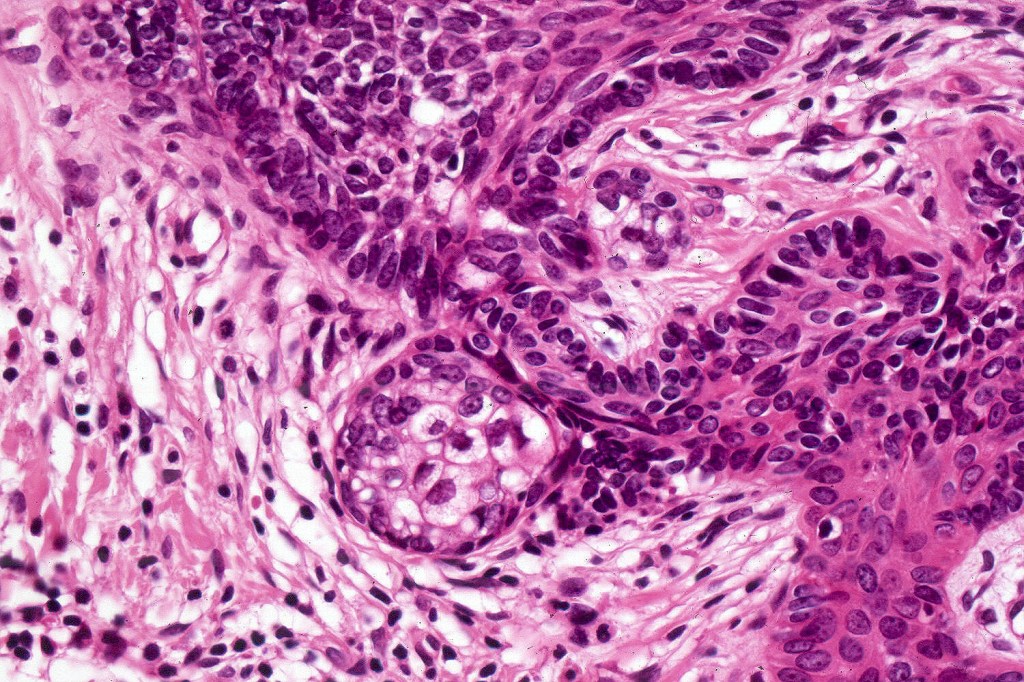

•Variably sized but generally large, basophilic tumor nodules composed of small uniform basaloid cells with minimal cytoplasm

•Variable mitotic activity, can be brisk

•No pleomorphism or abnormal mitoses

•Peripheral palisading but no retraction artifact or stromal mucin deposition

•A rich fibromyxoid mesenchymal stroma with variable papillary mesenchymal bodies (sometimes these are absent)